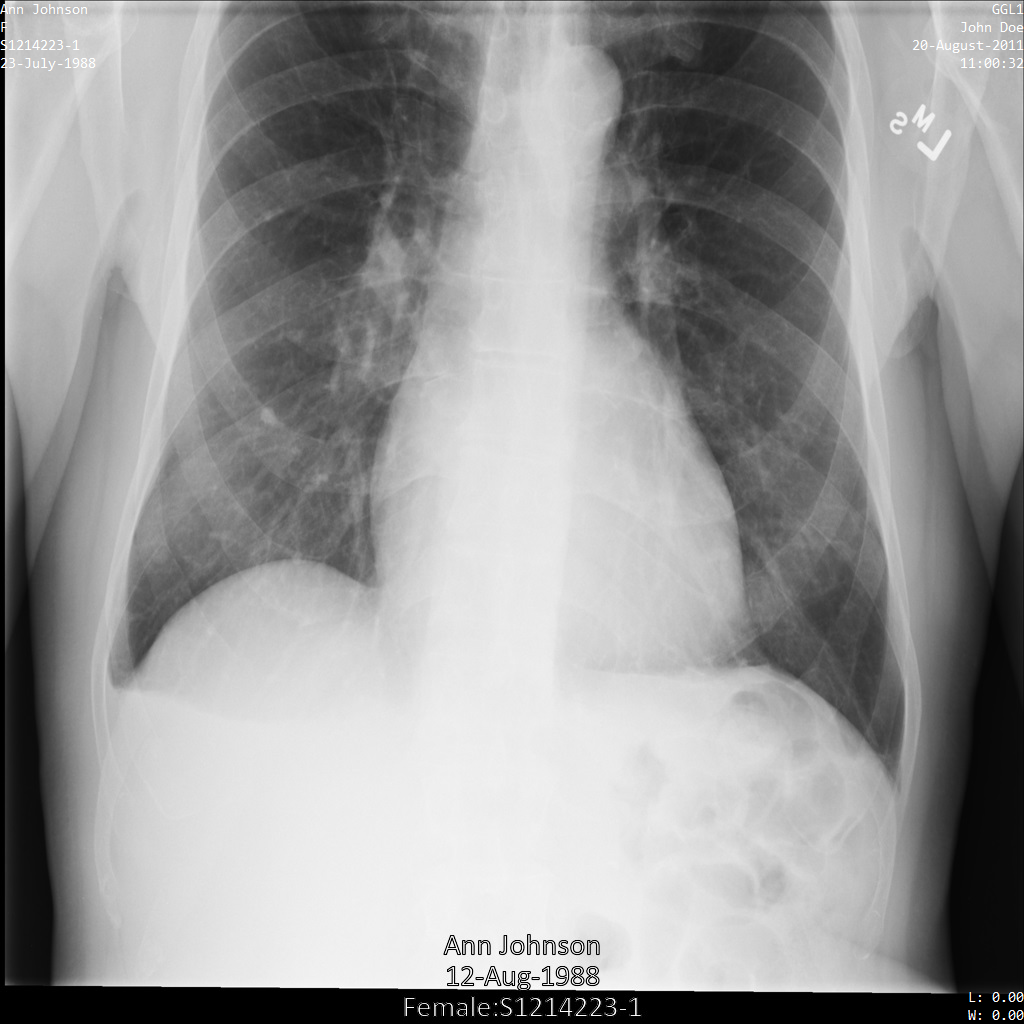

下圖顯示未經過編輯的病患 X 光片:

使用 REDACT_SENSITIVE_TEXT 選項將圖片提交給 Cloud Healthcare API 之後,圖片看起來會如下所示:

您可以看到發生了下列情況:

- 圖片左下角的

PERSON_NAME已遭塗銷 - 圖片左下角的

DATE已遭塗銷

由於根據預設 DICOM infoTypes,病患性別不屬於敏感文字,因此未經過修訂。